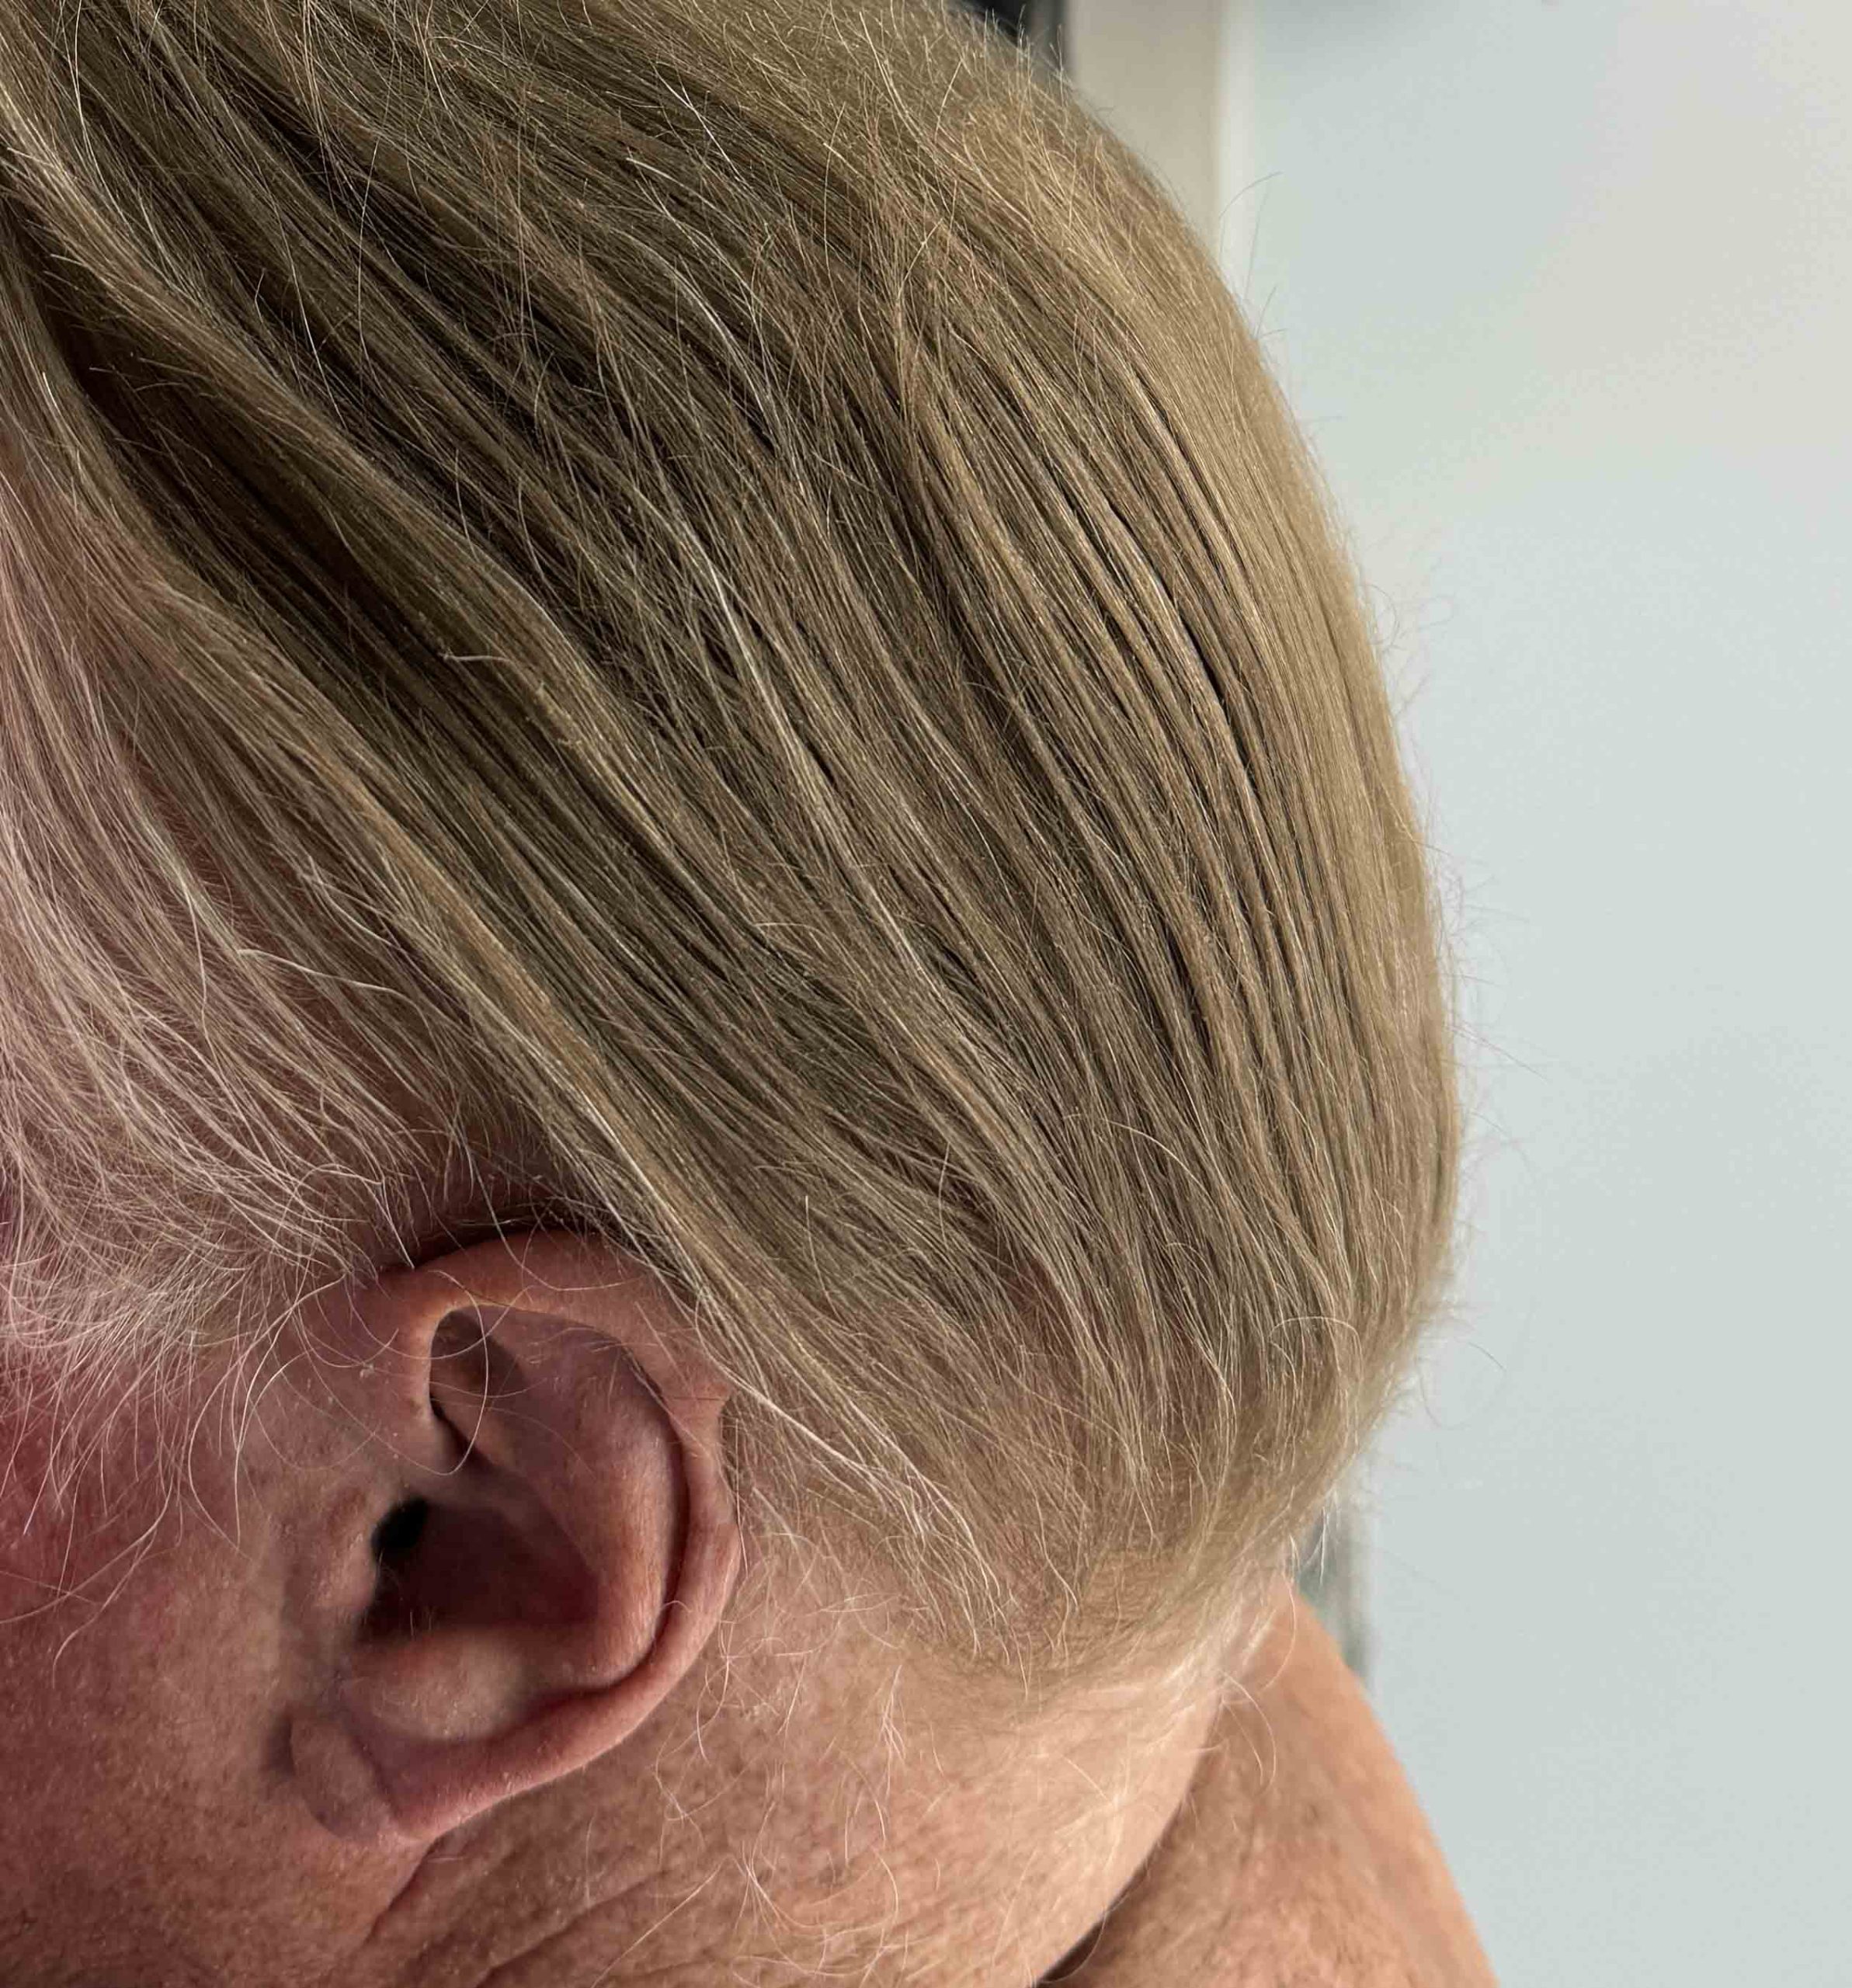

Older male with lifelong concerns about the flat back of his head.

Placement of custom back of head skull implant (120ccs) through a high scalp incision placed just under the hairline.

Older male with lifelong concerns about the flat back of his head.

Placement of custom back of head skull implant (120ccs) through a high scalp incision placed just under the hairline.